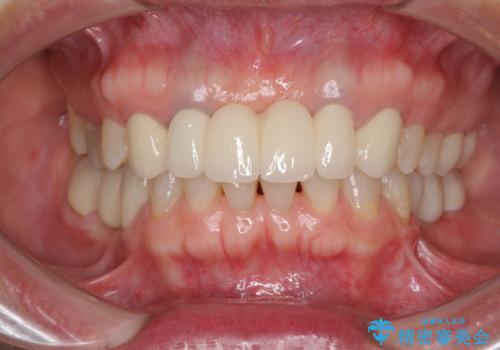

金属を使用した前歯のブリッジや奥歯の銀歯は全てオールセラミッククラウンまたはセラミックインレーとし、左下の奥歯はインプラントにより治療を行うこととしました。

遠方からの来院であったので、1回の治療時間を長めにし、できる限りの処置を集中して行うことで、来院回数を減らすことができました。

矯正治療までは考えていなかったそうですが、物が挟まっていた前歯のスペースがなくなり、矯正治療を行って良かったとのことでした。

初診カウンセリングを含めて13回の通院で治療を終えることができ、患者様には大変満足していただきました。